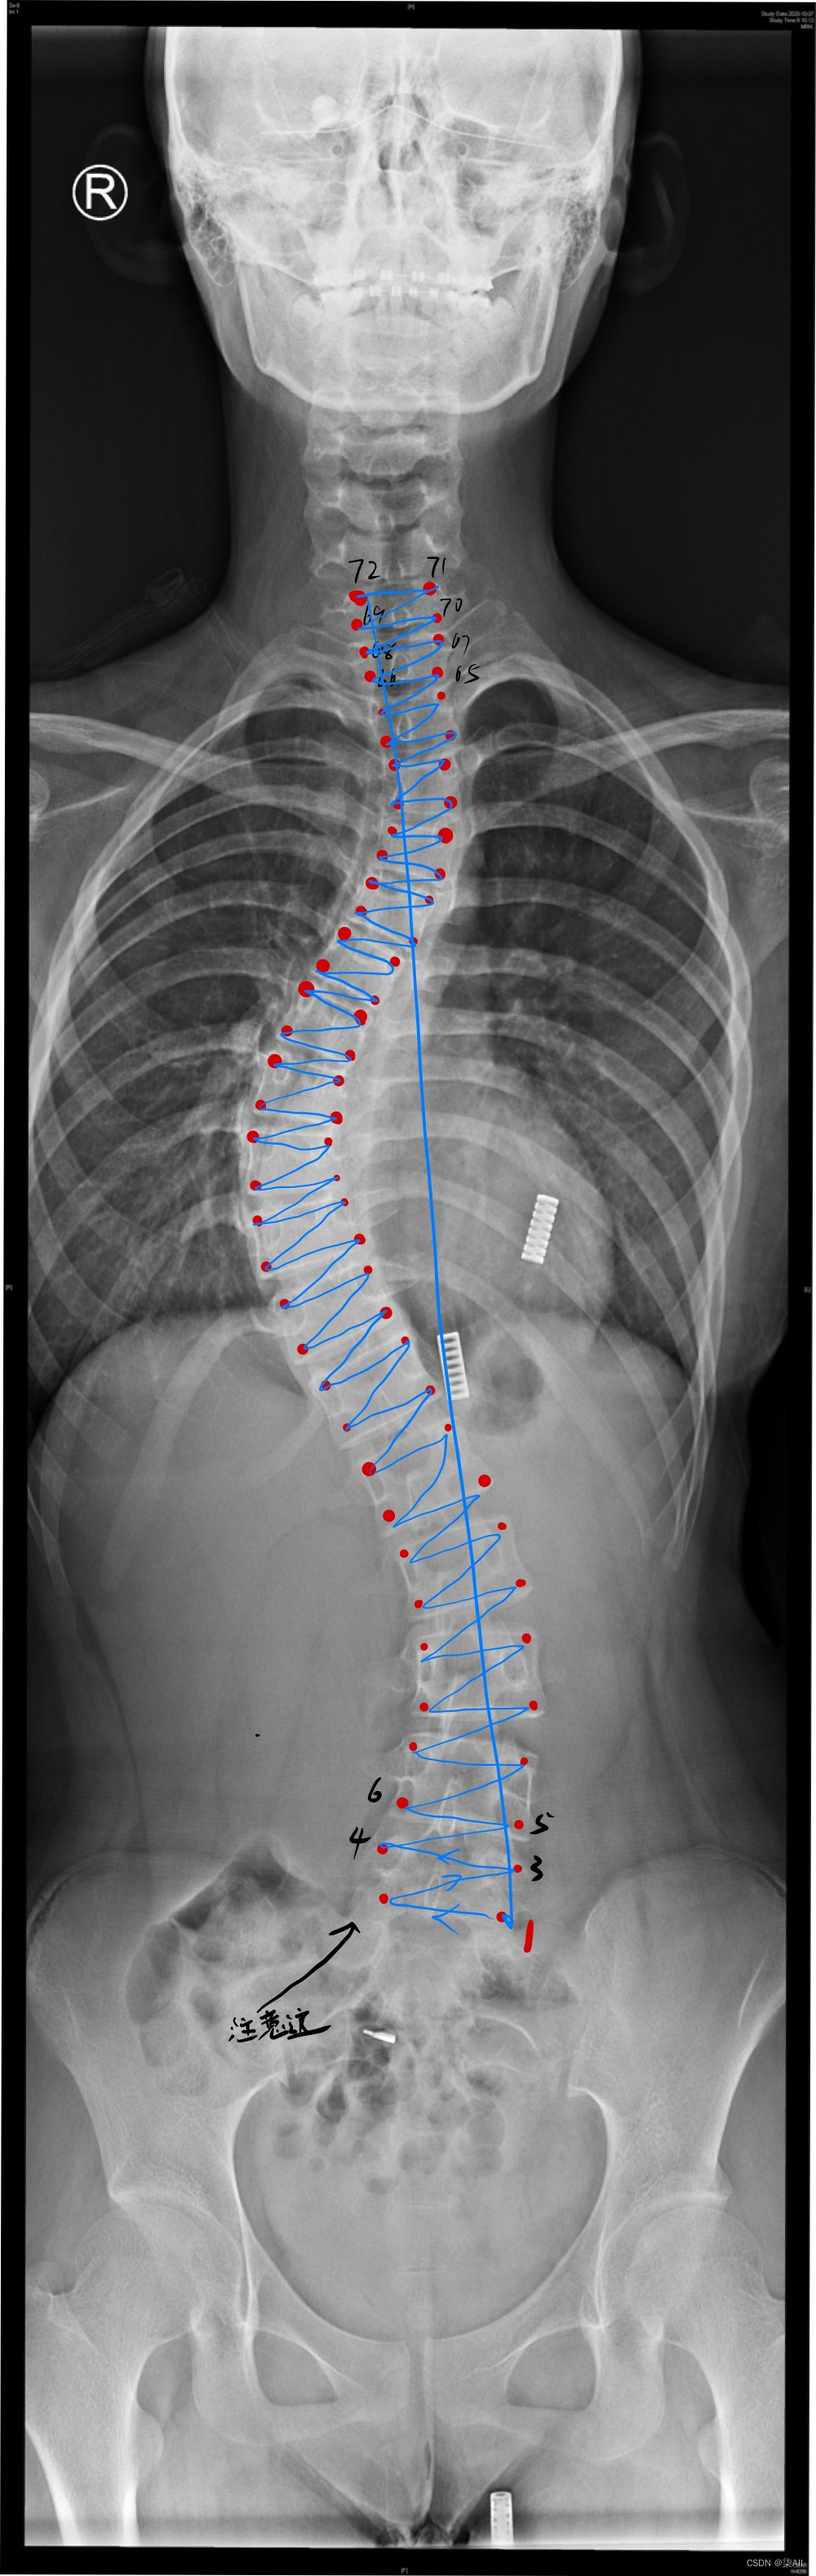

3、冠状位标注结果

4、标注过程注意事项

(1)标注的椎体应该近似是一个矩形,而不是梯形 如下图

(2)标注的时候关键点 不要(X)标记的太靠 边 ,但是 也不要往内收的太厉害

下图这个就不太行

(3)像这种椎骨不要变化太大,一般都是底下的椎骨大一些,往上逐渐减少,就因为看不清,所以得这样表

还是有很多问题的,这种计算cobb角肯定有问题,最后一个椎骨看不清,那画的线就与上一个椎骨平行,尽量平行标,要不然后面自动生成cobb角,误差很大,这样肯定不行,注意一下,认真一些,要不然得返修几次,不如好好弄,还节省时间

###(5) 参考AASCE2019 GT图

(6)你看这种58这种点,咱们可以往外标一点,或者把60缩一些